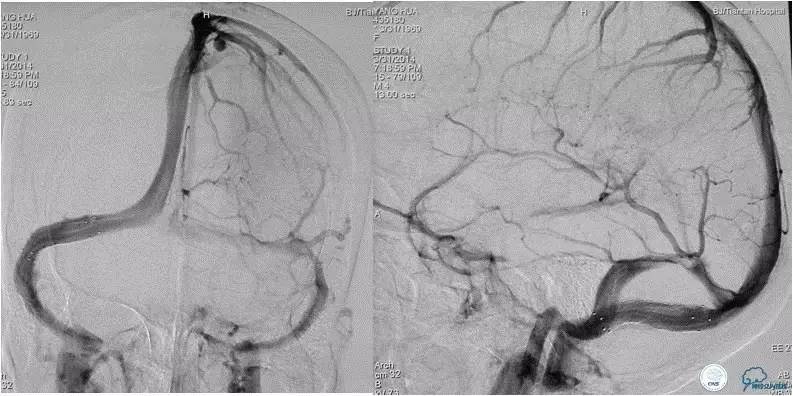

患者入院后,予以行脑动脉造影显示:右侧横窦和乙状窦交界区狭窄,左侧横窦和乙状长段重度狭窄(图3);经股静脉入路行右侧横窦和乙状窦测压显示狭窄两端压力差约为28 mmHg(图4)。遂予以阿司匹林100mg,每日一次,氯吡格雷75mg,每日一次。3d后在全麻插管下行右侧横窦-乙状窦交界处支架植入术。术中采用经右侧颈静脉入路,植入8~30mm 库克公司的ziliver支架,造影见右侧横窦-乙状窦交界处狭窄解除(图5),术中再次测压结果显示狭窄两端压力差约为1mmHg。术后自述双眼视物明显好转,但术后第3天眼底检查双视盘水肿较术前未见明显改善。

随访经过:3月后患者眼底检查双眼视盘水肿明显消退(图6),视力改善:右眼1.0,左眼0.4;8月后患者入院行脑血管造影(DSA)显示右侧横窦-乙状窦交界处支架通畅,未见再狭窄(图7)。

图5:术中经右颈静脉入路植入8-30mm库克公司ziliver支架,见右横窦-乙状窦交界处狭窄明显解除,术中测压显示狭窄两端压力差约为1mmHg 。

图7:术后8月随访患者,脑动脉造影显示右侧横窦-乙状窦交界处未见狭窄,支架内通畅良好,未见血栓形成和内膜增生。